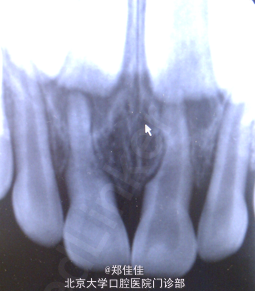

主诉:上前牙外伤2天余

诊断:51,61牙根外吸收+牙震荡 处置:密切观察,必要时拔除